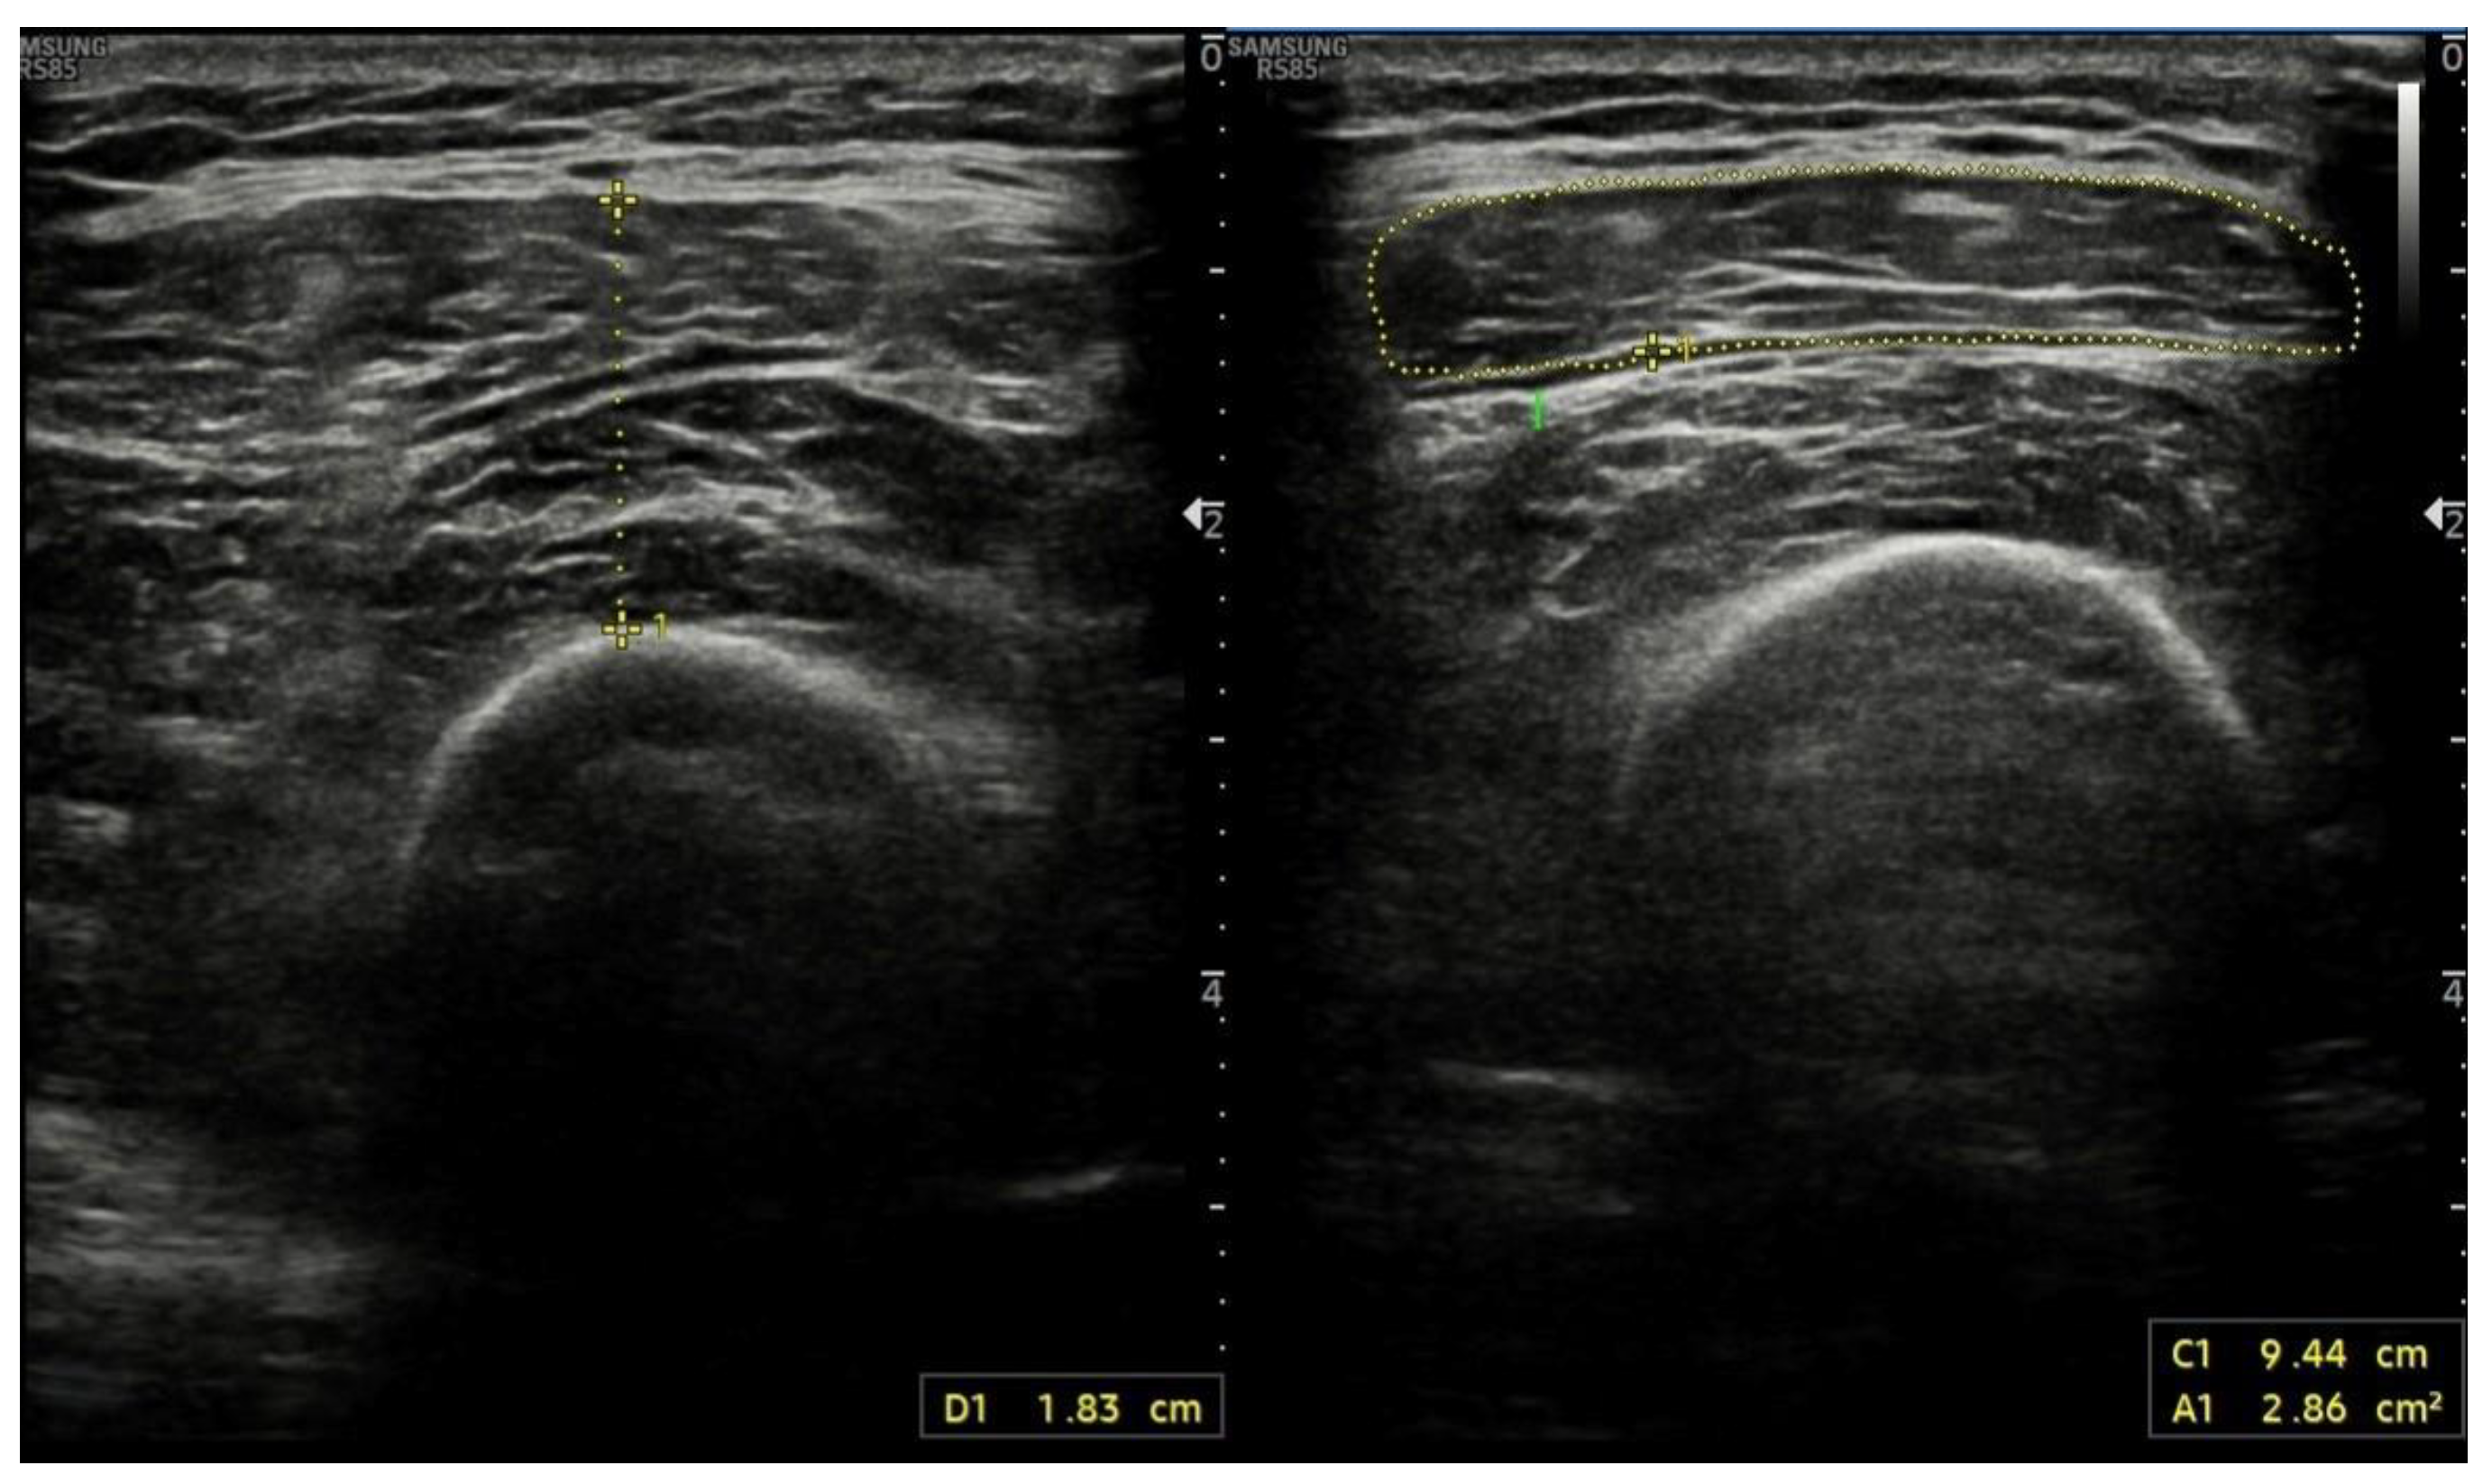

4.6. Ultrasound Assessment of Skeletal Muscle Tissues

- Gödiker, J.; Schwind, L.; Jacob, T.; Böhling, N.; Groba, S.N.R.; Kimmann, M.; Meier, J.A.; Peiffer, K.; Trebicka, J.; Chang, J.; et al. Ultrasound-Defined Sarcopenia Independently Predicts Acute Decompensation in Advanced Chronic Liver Disease. J. Cachexia Sarcopenia Muscle 2024, 15, 2792–2802. [Google Scholar] [CrossRef] [PubMed]

- Becchetti, C.; Berzigotti, A. Ultrasonography as a diagnostic tool for sarcopenia in patients with cirrhosis: Examining the pros and cons. Eur. J. Intern. Med. 2023, 116, 27–33. [Google Scholar] [CrossRef] [PubMed]

- Tandon, P.; Low, G.; Mourtzakis, M.; Zenith, L.; Myers, R.P.; Abraldes, J.G.; Shaheen, A.A.M.; Qamar, H.; Mansoor, N.; Carbonneau, M.; et al. A Model to Identify Sarcopenia in Patients With Cirrhosis. Clin. Gastroenterol. Hepatol. 2016, 14, 1473–1480. [Google Scholar] [CrossRef]

- de Luis Roman, D.; García Almeida, J.M.; Bellido Guerrero, D.; Rolo, G.G.; Martín, A.; Martín, D.P.; García-Delgado, Y.; Guirado-Peláez, P.; Palmas, F.; Pérez, C.T.; et al. Ultrasound Cut-Off Values for Rectus Femoris for Detecting Sarcopenia in Patients with Nutritional Risk. Nutrients 2024, 16, 1552. [Google Scholar] [CrossRef] [PubMed]

- Hari, A.; Berzigotti, A.; Štabuc, B.; Caglevič, N. Muscle psoas indices measured by ultrasound in cirrhosis—Preliminary evaluation of sarcopenia assessment and prediction of liver decompensation and mortality. Dig. Liver Dis. 2019, 51, 1502–1507. [Google Scholar] [CrossRef]